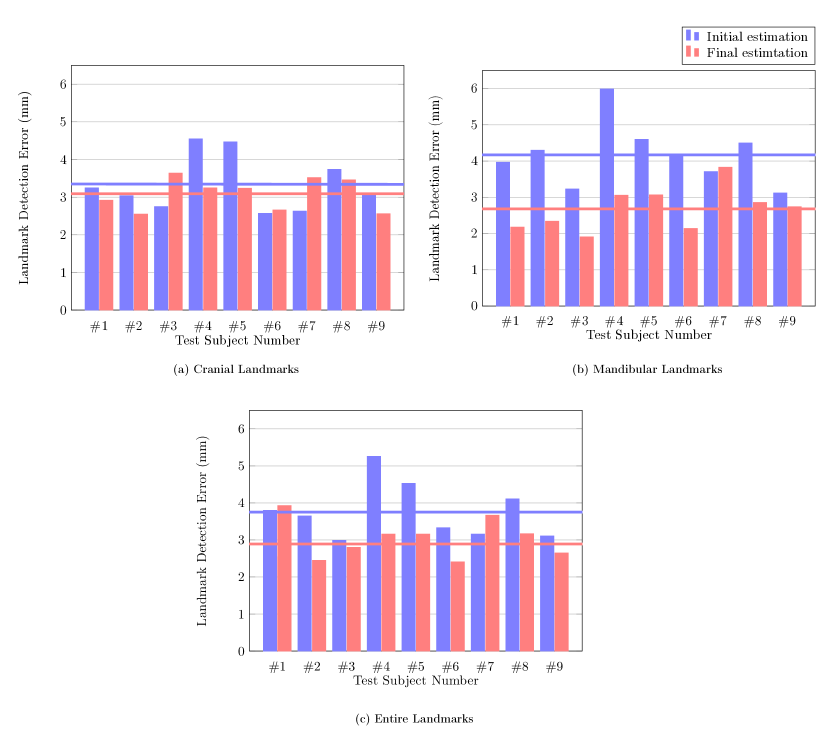

For each landmark, Figure 6 shows the performance evaluation achieved using 9 test data with respect to the averaged 3D point-to-point error. The mean detection error was 3.42 mm for the cranial landmarks (Figure 6(a)), 4.23 mm for the mandibular landmarks (Figure 6(b)), and 3.82 mm for all landmarks (Figure 6(c)). The error of the cranial landmark estimation was much smaller than that of the mandibular landmark estimation.

Figures 7(b) and 8(b) show the qualitative and quantitative results of the 3D CNNs. The mean 3D distance error decreased to 2.72 mm when compared to the initial detection error of 4.23 mm (Figure 6(b)). According to results shown in Table 3, the proposed method achieved an error range of 1 to 4 mm for the detection of most landmarks. In addition, as shown in Figure 10(b), the proposed method significantly reduced the mean and variance of error for the test subjects, compared to the initial detection.

Figures 7(a) and 8(a) show the final cranial landmark estimation results in qualitative and quantitative formats. The mean detection error for all cranial landmarks was 3.09 mm, which decreased from the initial estimation error of 3.68 mm (Figure 6(a)). As shown in Table 3, the error for most cranial landmarks fell within the range of 1 to 4 mm.